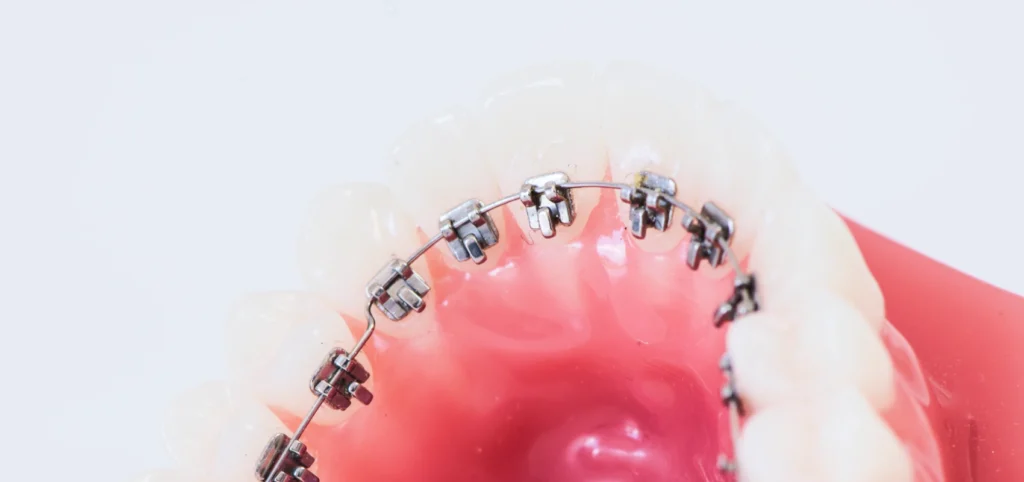

L’orthodontie et les appareils multi-attaches

Les appareils multi-attaches sont les plus répandus à l’adolescence. Ils se composent de petites attaches collées sur les dents et reliées entre elles par un fil fin. Ce fil exerce une tension douce pour repositionner les dents progressivement. Les attaches peuvent être métalliques ou en céramique, plus discrètes. Ce traitement, ajusté régulièrement, offre un contrôle précis du mouvement dentaire.

- Sa durée moyenne varie de 18 à 24 mois, selon la complexité du cas.

Une hygiène méticuleuse est essentielle pour éviter la plaque et les irritations. Ce dispositif reste une solution fiable pour obtenir un alignement harmonieux et durable.